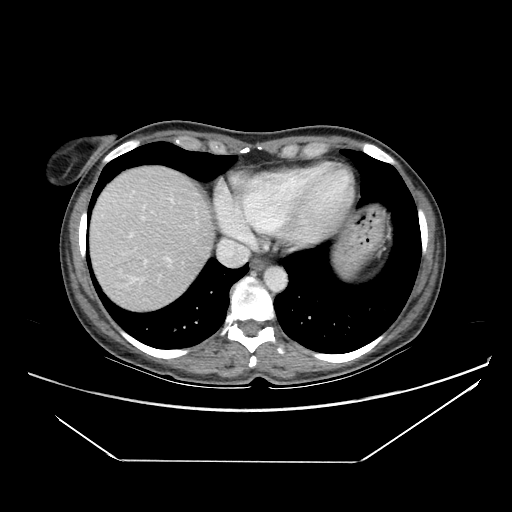

Image Grid

4Γ—3 grid: Rows show different image types (Original NATIVE, Reconstructed NATIVE, Original VENOUS, Generated VENOUS), Columns show windowing techniques (No Window, Lung Window, Mediastinum Window)

Original VENOUS CT scan

Full window (WL 1023.5, WW 4095 β†’ Low βˆ’1024, High +3071)

Lung window (WL -600, WW 1500 β†’ Low βˆ’1350, High +150)

Mediastinum window (WL 40, WW 400 β†’ Low βˆ’160, High +240)